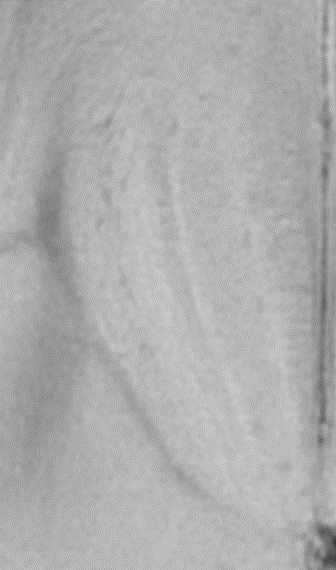

The BioSpec 180/11 is the ultimate in ultra-high-field MR imaging with unparalleled sensitivity for greatest resolution. Its streamlined design for mice studies makes handling simple, while its powerful software guarantees best results. It can be equipped with the MRI CryoProbe to increase sensitivity even further and together with the gradient strength of up to 1000 mT/m, highest resolution is achieved. It is built with Ultra Shielded and Refrigerated (USR) magnet technology for reduced maintenance costs and longer service intervals.

• Crisp and highly resolved images with native gradient strength of 740 mT/m, upgradable to 1000 mT/m

• MRI CryoProbe for exceptional increase in sensitivity